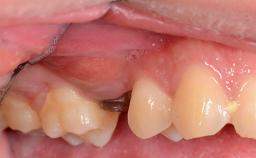

The patient presented with a failing tooth-supported fixed dental prosthesis with cantilever extension replacing the right maxillary central incisor. His chief presenting complaint was poor esthetics, in particular the dark discolored margin around the abutment tooth, the maxillary left central incisor. He reported a history of trauma at a young age, which necessitated the replacement of his maxillary right central incisor as well as root canal therapy of the adjacent left central incisor. The existing prosthesis had been in situ for over 20 years. The initial periapical radiograph displayed good proximal bone levels at the adjacent teeth and a wide incisive canal, which was a concern. The left central incisor presented a very wide root canal treatment with compromised radicular dentin thickness, which was a consideration in the decision between a new tooth-supported fixed dental prosthesis vs. an implant-supported prosthesis. After a lengthy discussion on the risks and benefits of both treatment options, the patient decided on a single-tooth implant replacement.